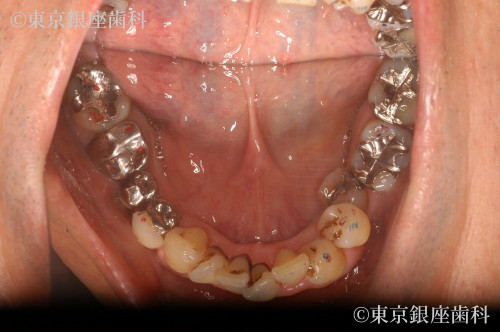

歯並びが悪く歯周病が進行していた

上部は審美治療を行い、下部はワンデイインプラントを行った